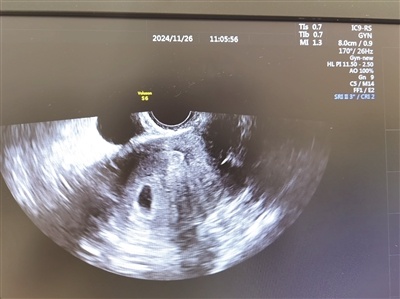

黄荷凤院士强调,第三代试管婴儿技术拥有阻断遗传致病基因的功能。以杜氏肌营养不良和血友病等单基因遗传病为例,浙江大学附属妇产科医院自90年代初便开展了相关研究。此技术为众多面临遗传病风险的家庭带来了新的希望,可在胚胎早期阶段对有害基因进行筛选。

黄荷凤院士研发了一项新技术。该技术能够对胚胎的多基因疾病遗传风险进行评估,具体做法是通过多基因遗传风险评分。基于此评估,团队筛选出风险最低的胚胎用于移植,从而实现对多基因遗传病的一级预防。经过家系验证和生殖伦理的审查,该团队以莺歌案例为试点,开始实施该技术,目标是为了向遗传性肿瘤的源头防控迈进。